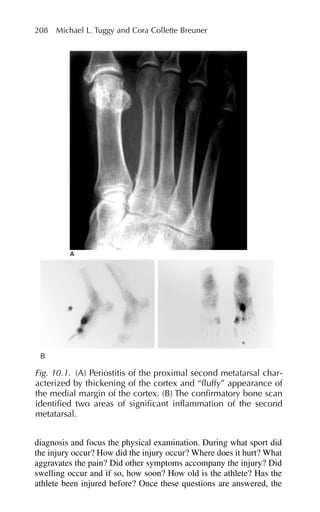

that contribute toaccelerated bone loss such as with hyperparathy- roidism, malignancy, renal failure, and hyperthyroidism.9 Assessment and Diagnosis Risk Factor Assessment Start with the medical history and ask questions about: Menopause (surgical and natural) Family history of osteoporosis (especially mother) Exercise Diet Smoking Alcohol intake Other risk factors such as age, gender, ethnicity, and slender body habi- tus can usually be observed without asking specific questions. The physical exam includes the measurement of height and weight, and the examination of the spine looking for any signs of deformity such as kyphosis, scoliosis, and limited range of motion. Screening for sec- ondary forms of osteoporosis may be helpful. Assess the patient’s risk of falling by asking about a history of falls and a decrease in visual acuity.10,11 Genetic Issues The prevalence of osteoporosis varies by sex, ethnicity, and race.12 Decreased bone density is more common in women of Northern European or Asian descent. Women and men experience age-related decrease in bone mass density starting at midlife, but women experi- ence more rapid bone loss after the menopause.13 Genetic syndromes like Turner’s (45,X0) syndrome patients have streak ovaries and decreased estrogen production leading to the early development of osteoporosis.14 Endocrine Factors Risk factors associated with decreased bone density include early estrogen deficiency secondary to surgery or to early menopause, hyperthyroidism, hyperparathyroidism, hypercortisolism, Addison’s disease, and Cushing’s syndrome.14 182 Paula Cifuentes Henderson and Richard P. Usatine

• 197.

Medications Chronic use ofcertain medications that affect the bone metabolism, such as corticosteroids, exogenous thyroid hormone, gonadotropin- releasing hormone (GnRH) analogues, anticoagulants, and anticon- vulsants, increase the risk of osteoporosis and subsequent fractures.15 Lifestyle Excessive use of alcohol depresses osteoblastic function and increases the risk of osteoporosis. Physical activity early in life contributes to higher peak bone mass and reduces the risk of falls by approximately 25%.16 Good nutrition with a balanced diet is necessary for the devel- opment of healthy bones. Calcium and vitamin D are required for the prevention and treatment of osteoporosis. There are data to support rec- ommendations (found later in the chapter) for specific dietary calcium intakes at various stages in life.17,18 Patients at high risk also include those who pursue thinness excessively, have a history of an eating dis- order,19 restrict their intake of dairy products, don’t consume enough vegetables and fruits, and have a high intake of low-calcium/high-phos- phorus beverages like sodas. These beverages have a negative effect on calcium balance. Laboratory Assessment If the history and physical exam suggests secondary causes of osteo- porosis, the physician should consider tests such as thyroid-stimulat- ing hormone (TSH), parathyroid hormone (PTH), calcium, vitamin D, urine N-teloptide, complete blood count (CBC), chem panel, cortisol, erythrocyte sedimentation rate (ESR), or serum protein electrophore- sis, based on the differential diagnosis.20,21 Bone Densitometry Assessment To prevent osteoporosis, the physician should attempt to establish early detection of low bone mineral density (BMD). Currently there is no accurate measure of bone strength, but BMD is the accepted method to establish a diagnosis of osteoporosis and predict future fracture risk.22,23 The World Health Organization (WHO) defines osteoporosis as a BMD 2.5 standard deviations (SDs) below the mean for young white adult women. This definition does not apply to other ethnic groups, men, or children.7,24 The U.S. Preventive Services Task Force suggests that the primary reason to screen postmenopausal 8. Osteoporosis 183

• 198.